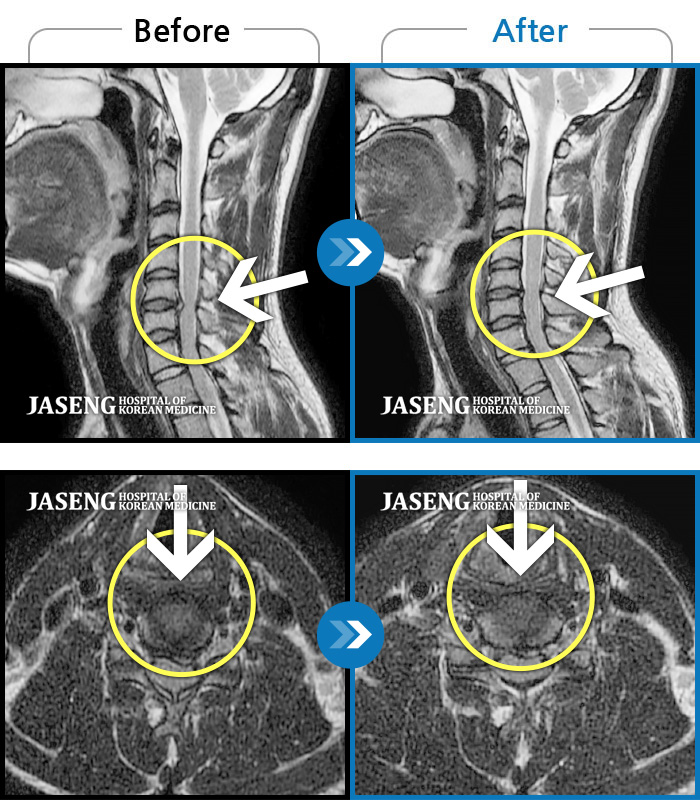

목디스크

도움받은 사례

인천 · 강아현 원장

목 통증 및 좌측 팔 저림으로 숨 쉬는 것도 불편하고 움직일 수가 없는 상태로 내원하셨습니다.

촬영시기

2023.02.13 ~ 2023.09.14

2023.09.15

조회수 111